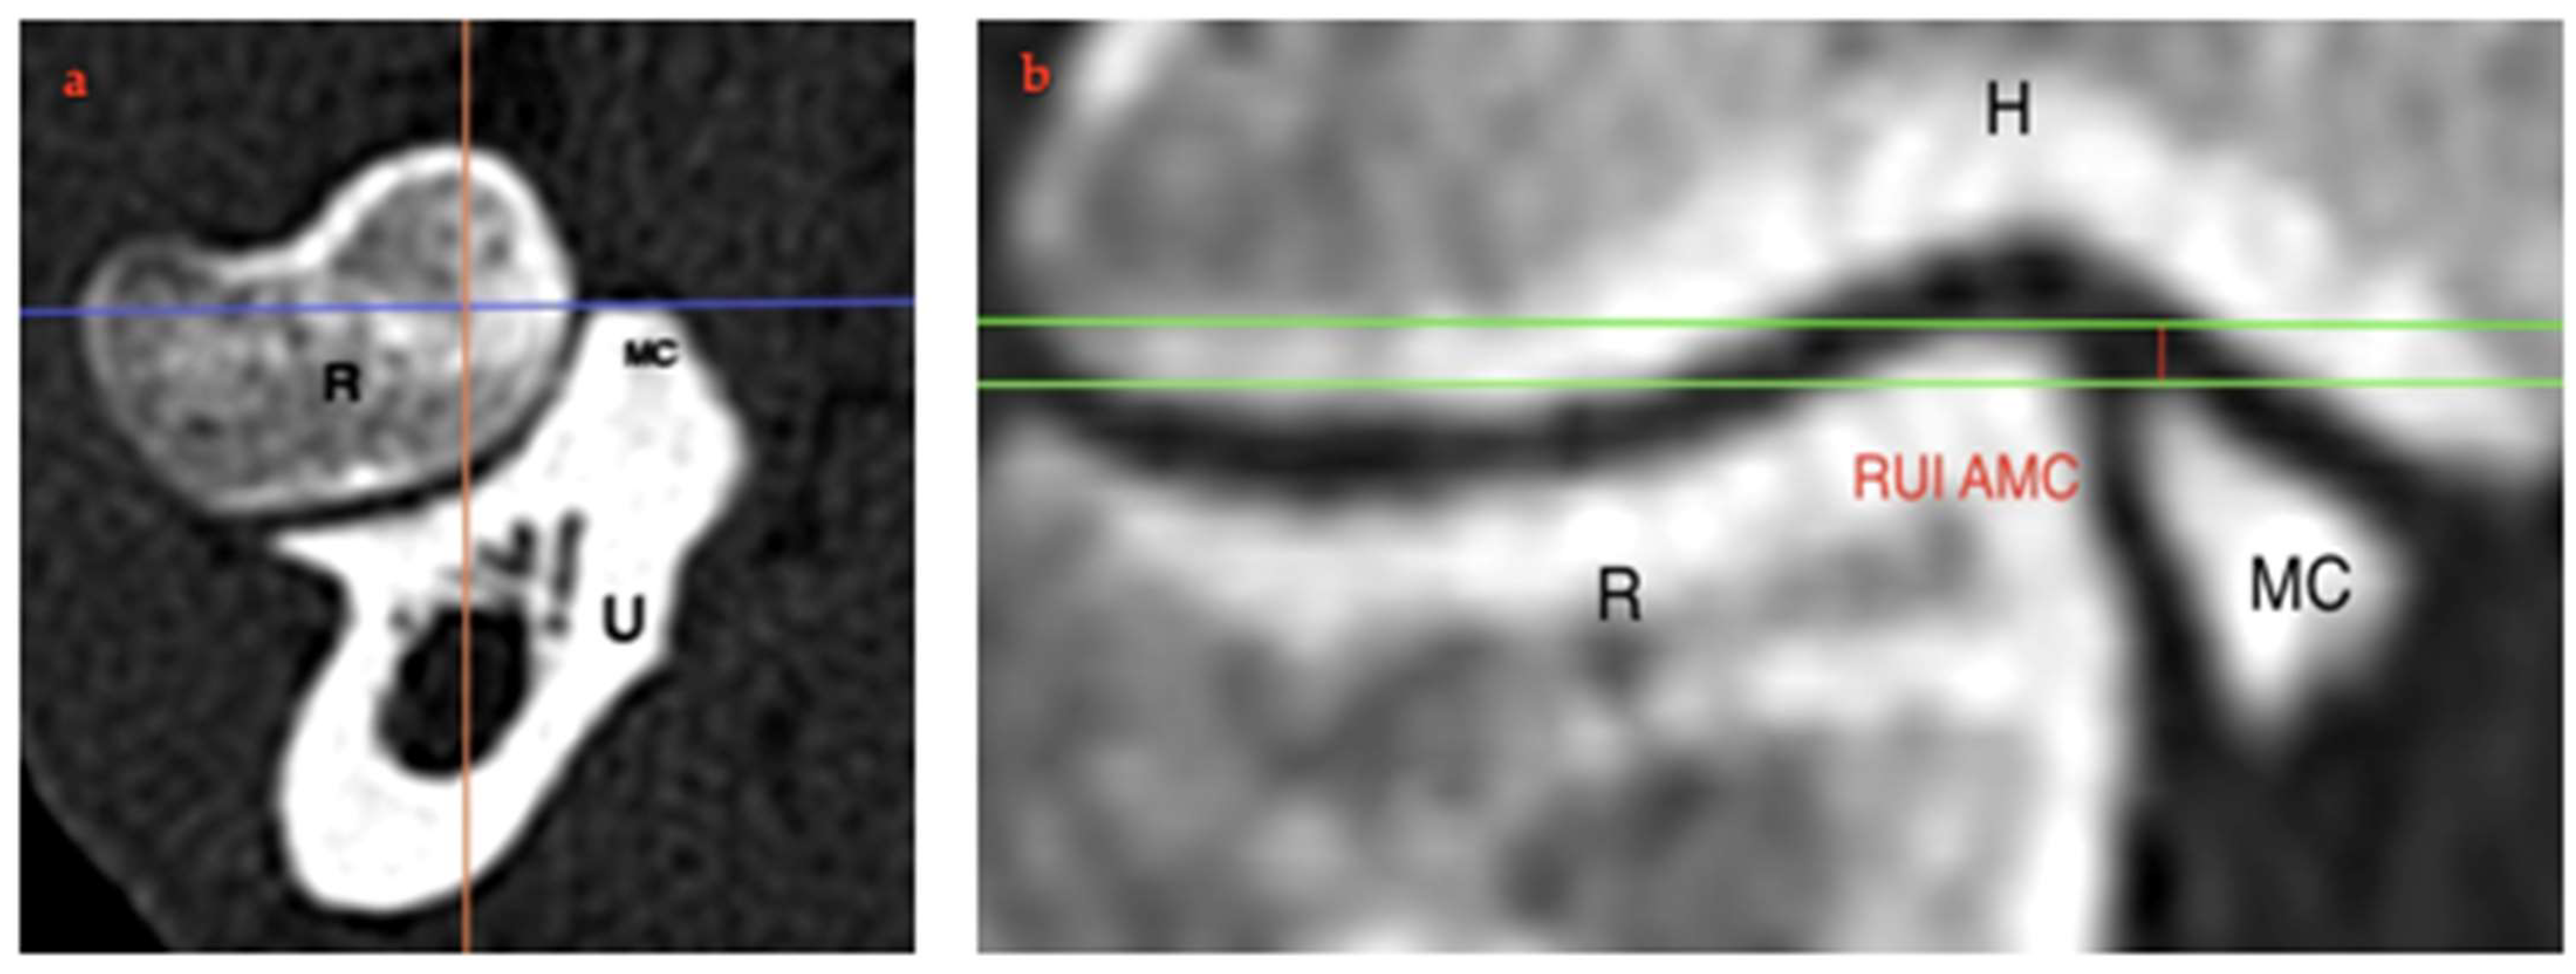

2.4. RUI Measurements